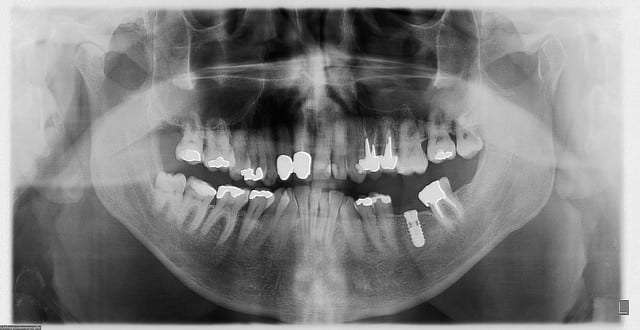

cette réflexion, c'était tout simplement: "on arrive à planifier au 1/10mm sur les logiciels la pose des implants et on est ensuite quasi incapable de les transposer à main levée lors de la chirurgie"...

avec Béo, patmo et quelques autres nonoliens, on s'y est attelé, à la réalisation d'un protocole d'utilisation de logiciels open source pour pouvoir nous même, avec un investissement raisonnable (comptez environ 4000€ pour une imprimante 3D et un VRAI ordi) faire nos guides à des tarifs imbattables (allez, pour rigoler, environ 2€ de plastique...)

c'est peut être pas aussi précis que ce que peut faire Posit, mais c'est déjà pas si mal...;-)

heu, non, tu confonds...on s'est amusé à faire tout un protocole avec les logiciels suivants:

invesalius pour lire les dicom

meshlab pour nettoyer les artefacts

blender pour planifier et créer les fichiers stl permettant la réalisation d'un guide chir grâce à une imprimante 3D

Parcontre j'ai vite compris que pour obtenir une precision correcte il faut scanner un model et le superposer à l'arcade rendu en 3D, il faut donc avoir aussi un scanner de IAO